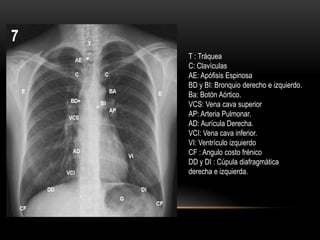

T : Tráquea

C: Clavículas

AE: Apófisis Espinosa

BD y BI: Bronquio derecho e izquierdo.

Ba: Botón Aórtico.

VCS: Vena cava superior

AP: Arteria Pulmonar.

AD: Aurícula Derecha.

VCI: Vena cava inferior.

VI: Ventrículo izquierdo

CF : Angulo costo frénico

DD y DI : Cúpula diafragmática

derecha e izquierda.

T : Tráquea C:Clavículas AE: Apófisis Espinosa BD y BI: Bronquio derecho e izquierdo. Ba: Botón Aórtico. VCS: Vena cava superior AP: Arteria Pulmonar. AD: Aurícula Derecha. VCI: Vena cava inferior. VI: Ventrículo izquierdo CF : Angulo costo frénico DD y DI : Cúpula diafragmática derecha e izquierda.

• #10 Paredes del tóraxCOLUMNA VERTEBRAL: los cuerpos vertebrales se ven en forma borrosa, y las apófisis espinosas (AE), dispuestas a lo largo de la línea media, se aprecian mejor en la parte alta del tórax, perdiéndose detrás del corazón. En la proyección lateral las vértebras se ven más claramente, viéndose más blancas las superiores por la sobreposición de las masas musculares de la cintura escapular.COSTILLAS: por su trayecto oblicuo los arcos posteriores de las costillas se proyectan varios centímetros más arriba que sus extremos anteriores, que son los más fáciles de individualizar para contar las costillas. Sus bordes son aproximadamente paralelos, y los espacios intercostales son iguales a ambos lados del tórax. En personas de edad, los cartílagos costales suelen calcificarse, dando imágenes que pueden confundirse con lesiones patológicas del pulmón.ESTERNON: se ve en su totalidad en la proyección lateral (ET), mientras que en frontal sólo se ve la zona del manubrio por encima de la extremidad de la segunda costilla. Ocasionalmente puede aparentar un ensanchamiento de la parte alta del mediastino. CLAVICULA: es importante individualizar sus extremos internos (C) en relación a las apófisis espinosas para verificar si la placa esté bien centrada.ESCAPULA: al tomarse una radiografía, los brazos se ponen en posición tal que las escápulas (E) son desplazadas fuera del campo de proyección de los pulmones, pero generalmente es posible ver su borde interno proyectado sobre éstos. DIAFRAGMA: En inspiración profunda la parte más alta de la cúpula diafragmática derecha (DD) coincide aproximadamente con el extremo anterior de la 6� costilla. Debido al peso del corazón, la cúpula izquierda (DI) está 1,5 a 2,5 cm más abajo en el 90% de los sujetos normales. Usualmente las cúpulas son regularmente redondeadas, pero pueden presentar lobulaciones. A ambos lados contactan en ángulo agudo con las paredes costales formando los senos costofrénicos laterales (CF). Hacia la línea media, la cúpula derecha termina formando con el corazón el ángulo cardiofrénico, mientras que a la izquierda puede seguirse por varios centímetros dentro de la sombra cardíaca. Uno a dos cm bajo el diafragma izquierdo se observa la burbuja de aire del estómago (G), relación que sirve para reconocer la posición de pies en la placa frontal, identificar este hemidiafragma en la radiografía lateral y para sospechar, como más adelante veremos, la existencia de un derrame infrapulmonar al lado izquierdo. En esta última proyección puede apreciarse que, por tener las inserciones posteriores del diafragma una posición más caudal, los senos costofrénicos posteriores (CFP), están situados varios centímetros por debajo de los anteriores y laterales y son los primeros que se borran al iniciarse un derrame pleural..PARTES BLANDAS PARIETALES. Usualmente su situación externa al tórax es evidente pero, en ocasiones, los pezones y tumores superficiales pueden simular nódulos, mientras que los pliegues cutáneos pueden dar falsas imágenes lineales. Las mamas voluminosas pueden producir un velamiento tenue y una mastectomía, una falsa imagen de hipertranslucencia pulmonar.Contenido torácicoTRAQUEA: en la placa frontal se ve como una tenue columna aérea (T) que baja por la línea media, desviándose ligeramente a la derecha a nivel del cayado aórtico. En la radiografía lateral es levemente oblicua de delante a atrás.BRONQUIOS PRINCIPALES: en la placa frontal, un poco por debajo del nivel del botón aórtico, se separan las columnas aéreas de los bronquios derecho (BD) e izquierdo (BI), formado una carina de ángulo variable entre 50 y 100%.En proyección lateral, estos bronquios principales se superponen y no son diferenciables, pero las ramas para los lóbulos superiores de ambos pulmones (BSD y BSI) siguen un trayecto horizontal, relativamente paralelo al haz de rayos, por lo que sus paredes son atravesadas longitudinalmente y contrastan como claridades redondeadas superpuestas al eje traqueal, siendo la más alta la correspondiente al bronquio derecho. Las ramas bronquiales lobulares y sus subdivisiones no son visibles por estar rodeadas de pulmón lleno de aire.MEDIASTINO: Los órganos centrales del tórax forman una silueta característica en la placa frontal, cuyo borde derecho está formado de arriba abajo sucesivamente por el tronco braquiocefálico derecho, la vena cava superior (VCS), la aurícula derecha (AD) y una pequeña parte de la vena cava inferior (VCI). El borde izquierdo empieza arriba con la arteria subclavia y sigue con la prominencia del botón aórtico (BA). En la parte media se proyecta el tronco de la arteria pulmonar(AP), parte de la aurícula izquierda y finalmente, el ventrículo izquierdo (VI), que forma un arco fuertemente prominente. En la placa lateral la sombra cardíaca descansa y se confunde con la mitad anterior del hemidiafragma izquierdo. Su borde anterior está formado por el ventrículo derecho (VD) y el posterior por la aurícula izquierda arriba, el ventrículo al medio y la vena cava inferior, abajo. El cayado aórtico (CA) puede distinguirse parcialmente como un arco anteroposterior.PARENQUIMA PULMONAR. El aire, las paredes bronquiales, los tabiques alveolares y el intersticio normales no dan imagen radiográfica notoria. La trama que se ve en los campos pulmonares corresponde a los vasos pulmonares llenos de sangre que contrastan con el parénquima aireado. Las arterias pulmonares y el nacimiento de sus ramas principales forman parte del mediastino y de las sombras hiliares. Hacia la periferia, las arterias (A) se ven más tenues, pero es posible seguirlas hasta 1 a 2 cm de la pleura y apreciar sus divisiones, que se suceden con intervalos de 1 a 2 cm. Por efecto de la gravedad, la presión hidrostática intravascular es mayor en las bases, por lo cual los vasos en estas zonas están más distendidos y se ven un 50 - 75% más gruesos que los de la mitad superior del pulmón. En la mitad inferior de los pulmones, las arterias siguen un trayecto oblicuo cercano a la vertical, mientras que las venas siguen una dirección casi horizontal hacia la aurícula izquierda.Los bronquios iintrapulmonares no se ven por constituir prácticamente una interfase aire-aire. Ocasionalmente pueden dar origen a una imagen anular cercana a los hilios cuando los rayos los atraviesan a lo largo de su eje longitudinal.HILIOS PULMONARES. Anatómicamente son el conjunto de vasos, bronquios, nervios que desde el mediastino penetran al pulmón, más algunos ganglios linfáticos pequeños. Su principal componente radiográfico al lado derecho son las ramas de la arteria pulmonar derecha, mientras que al lado izquierdo son la arteria pulmonar izquierda en sí misma y sus divisiones. En condiciones normales, los demás componentes contribuyen poco a las sombras hiliares. El hilio derecho se encuentra aproximadamente 1,5 cm más bajo que el izquierdo.PLEURAS. En la mayor parte de su extensión, estas membranas se encuentran en contacto con la superficie interna del tórax, formando una interfase sólido-sólido, que no da imagen radiográfica. A nivel de las cisuras pulmonares, en cambio, la pleura tiene aire por ambos lados, de manera que da origen a una fina imagen lineal en las zonas en que los rayos la atraviesan tangencialmente. La cisura menor u horizontal del lado derecho se ve frecuentemente en la radiografía frontal y casi siempre en la lateral. Las cisuras mayores u oblicuas (CO) no son apreciables en la placa frontal, pero suelen verse en la lateral como finas líneas oblicuas de atrás a adelante y de arriba a abajo.Tamaño del pulmónEl tamaño de los pulmones se aprecia en la radiografía especialmente por la posición del diafragma y mediastino y por la conformación de la caja torácica. Varía ampliamente con la contextura y talla del individuo. En posición de pies y en inspiración profunda, el vértice de la cúpula diafragmática derecha coincide con el extremo anterior de la 5a a 6a costilla. Al lado izquierdo la base pulmonar está, en general, hasta 2,5 cm más bajo. En decúbito el tórax se acorta considerablemente, el corazón se dispone más horizontalmente y el mediastino se ensancha. Lo mismo sucede, en menor grado, en la espiración. En alteraciones unilaterales el mediastino suele desplazarse hacia el pulmón de menor tamaño al tiempo que los espacios intercostales de ese lado se ven más estrechos.